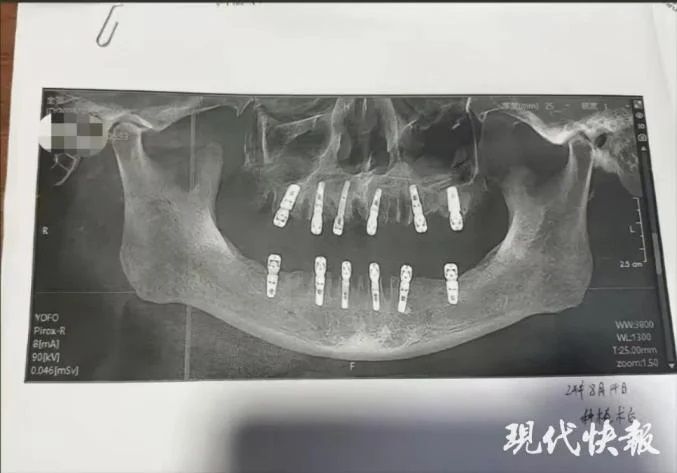

تحقق السلطات الصينية في قضية رجل مسن توفي بعد 13 يومًا من خلع 23 سنًا وزرع 12 سنًا جديدة في نفس اليوم في عيادة أسنان، وهو الأمر الذي دفع ابنته لتقديم شكوى ضد عيادة الأسنان التي قامت بهذا الإجراء المفرط.

وقدمت الابنة واسمها شو، من مقاطعة تشجيانغ الصينية، شكوى مؤخرًا إلى مكتب الصحة البلدي ضد عيادة الأسنان مع أدلة على أن والدها خلع 23 سنًا وزرع 12 سنًا جديدة في جلسة واحدة، والتي تدعي أنها تسببت في وفاته المفاجئة بعد 13 يومًا.

وأخبرت شو السلطات أن والدها عانى من آلام مبرحة طوال الأيام الثلاثة عشر الأخيرة من حياته، قبل أن يعاني من نوبة قلبية قاتلة في 28 أغسطس. والآن تريد المرأة تقديم المسؤولين إلى العدالة. ووفقًا لنموذج موافقة المريض، فقد حصل والد شو بالفعل على خلع 23 من أسنانه الطبيعية قبل حفر 12 ثقبًا في جمجمته وفكه لزراعة أسنان جديدة. تم إجراء كل هذا في يوم واحد، مما يعني أنه كان عليه أن يتحمل آلامًا لا يمكن تصورها بعد زوال تأثير التخدير. وعلى الرغم من أن عدد عمليات الخلع يبدو مفرطًا بعض الشيء لجلسة واحدة، إلا أن المتحدث باسم العيادة التي أجريت فيها العملية قال إن عدد الأسنان التي يمكن إزالتها في المرة الواحدة يجب أن يحدده الطبيب في استشارة وجهاً لوجه بناءً على الحالة الجسدية للمريض.